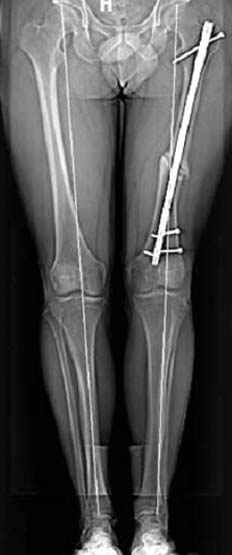

Несколько снимков из моей коллекции, чтобы разьяснить, почему мы до сих пор делаем различные варианты остеотомии.

N3 рисунок окончательный снимок, после операции моя рентгенограмма должен выглядеть примерно как эта картина. На N4 снимке клин перед удалением; N5 послеоперации 3 нед.; N6 окончательная рентгенограмма.

пластическая модель; и коррекция бедра аппаратом Илизарова.